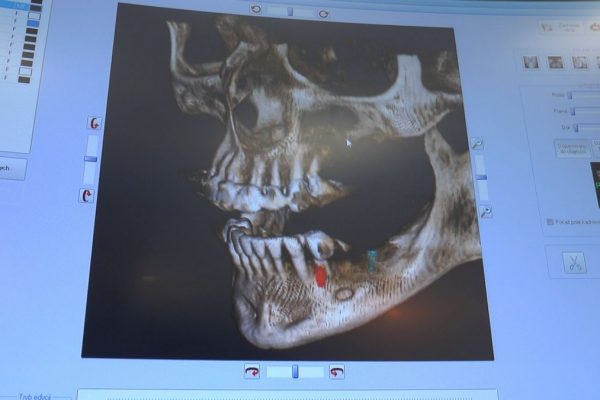

W ostatni weekend czerwca 2018 roku kursanci II Sezonu Preludium Implantologii odbyli piątą, finałową sesję, która w całości podporządkowana była praktyce. W ciągu dwóch dni zabiegowych Lekarze uczestniczący w szkoleniu przeprowadzili szereg zabiegów pod kierunkiem dr n.med. Violetty Szycik. Wszczepili 17 implantów oraz przeprowadzili ekstrakcje i zabiegi regeneracyjne kości. Zabiegi były wykonywane także w sedacji dożylnej z udziałem specjalisty anestezjologii i intensywnej terapii dr Jolanty Grzybowskiej. Preludium implantologii to nowy program edukacyjny dla adeptów implantologii stomatologicznej, którego celem jest wprowadzenie do implantologii poprzez pozyskanie wiedzy w szerokim zakresie i uwzględnieniem szczegółów mających decydujące znaczenie dla powodzenia leczenia implantologicznego. Ale tak jak wszystkie szkolenia w Instytucie Vivadental, w tym wiodące Practiculum Implantologii, zorientowane jest na praktyce i samodzielnym wykonywaniu zabiegów pod kierunkiem Mentora. To najlepsza edukacja w medycynie zabiegowej, a zarazem najlepszy start do implantologii.